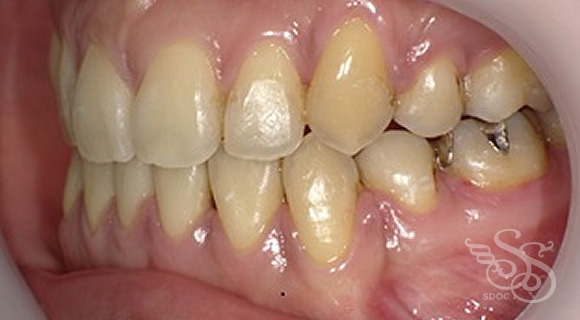

久しぶりに会った友人に「整形した?」と言われた患者さま

術前

術後

この症例をもっと詳しく見る